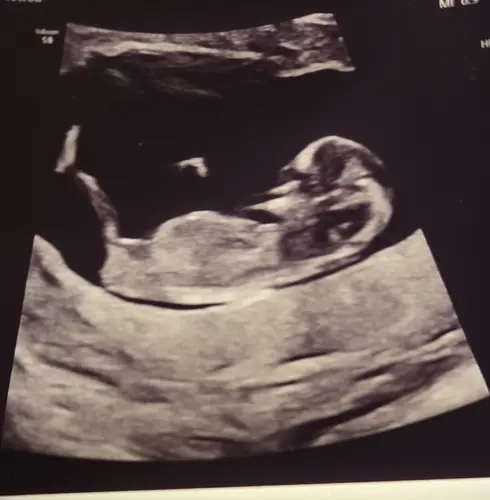

Dit was met 11 weken!

Jongetje… hoewel nog vroeg, zie je wel al een stijgende nub.